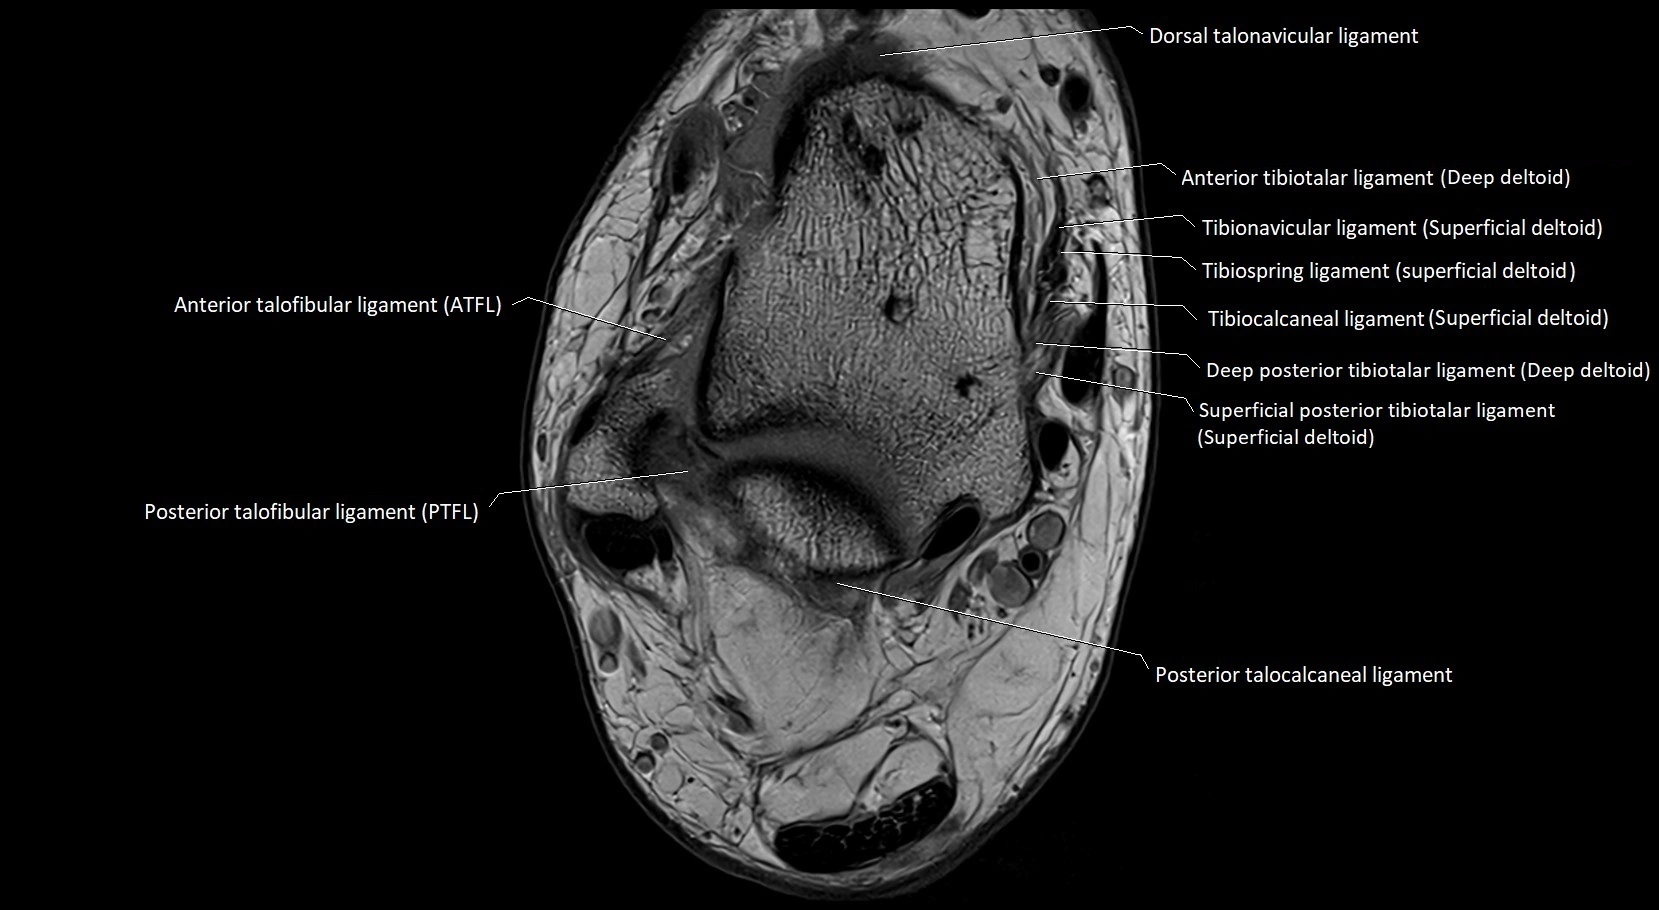

MRI image

image